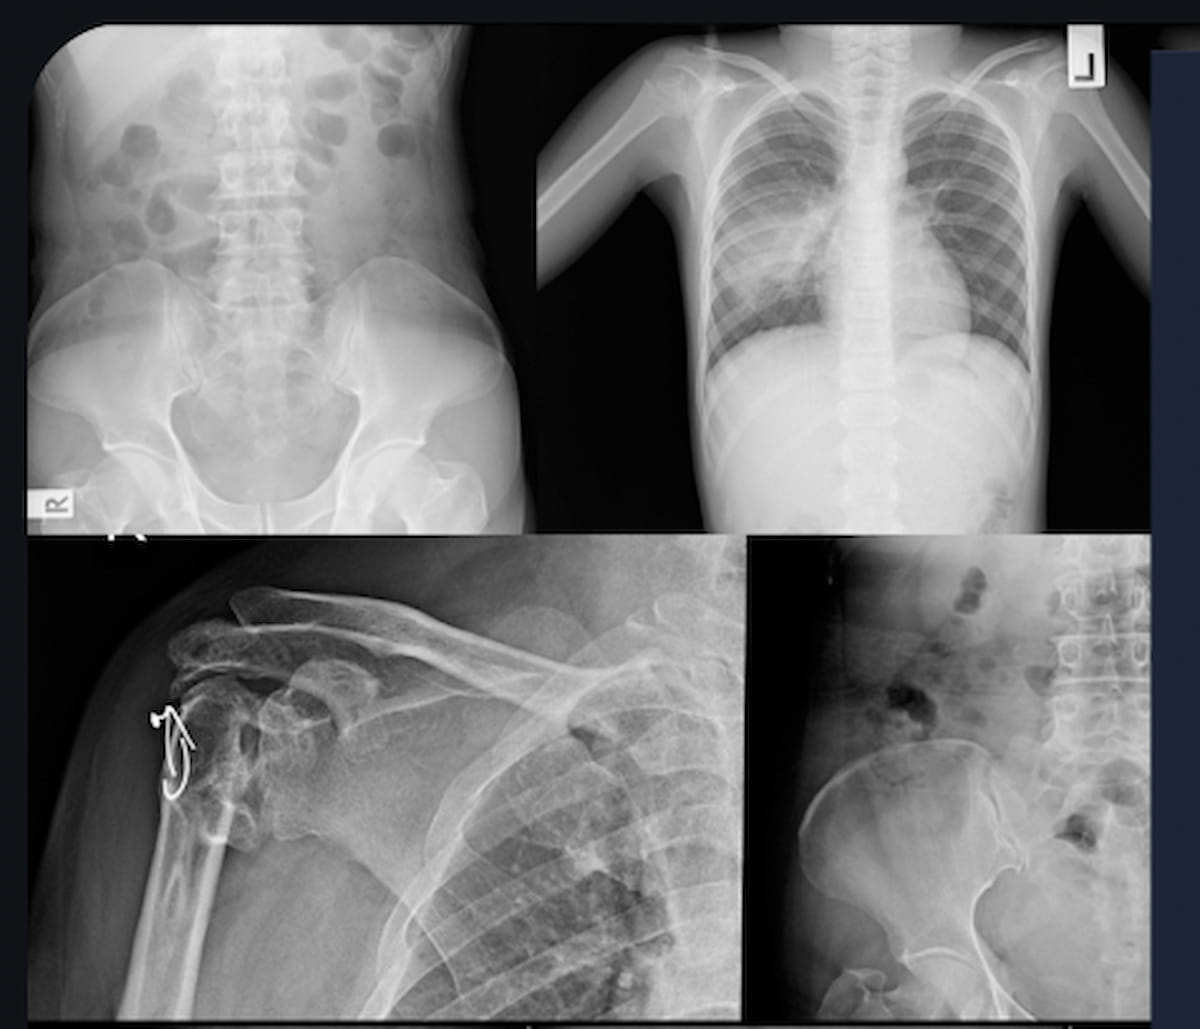

Employing reconstructed radiographs from 3D hip CT scans, a deep learning model demonstrated a higher concordance index (C index) and higher two- and three-year AUCs than multiple imaging models and three clinical models for predicting subsequent fracture risk in patients with hip fractures.